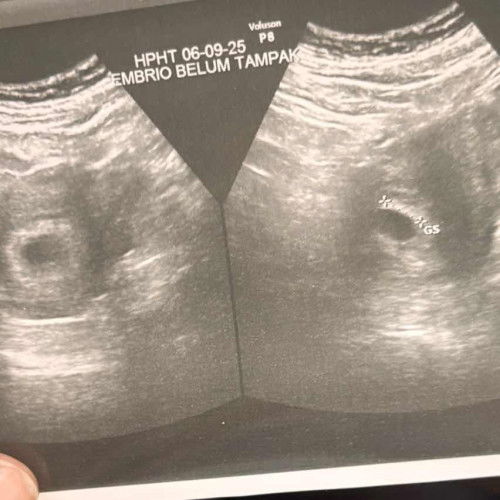

perut dari kemarin keras kadang nyeri bagian bawah sampe punggung dan kentut kentut tapi bab ga mau kluar apa itu kontraksi? tapi ga kluar lendir atau flek apapun..hamil 38 minggu... kalo bener kontraksi sebaiknya ngapain? senam untuk buka panggul apa lebih baik istirahat aja#SeriusTanya #Sharing_dong_Bund #newmom #firstmom #ingintahu